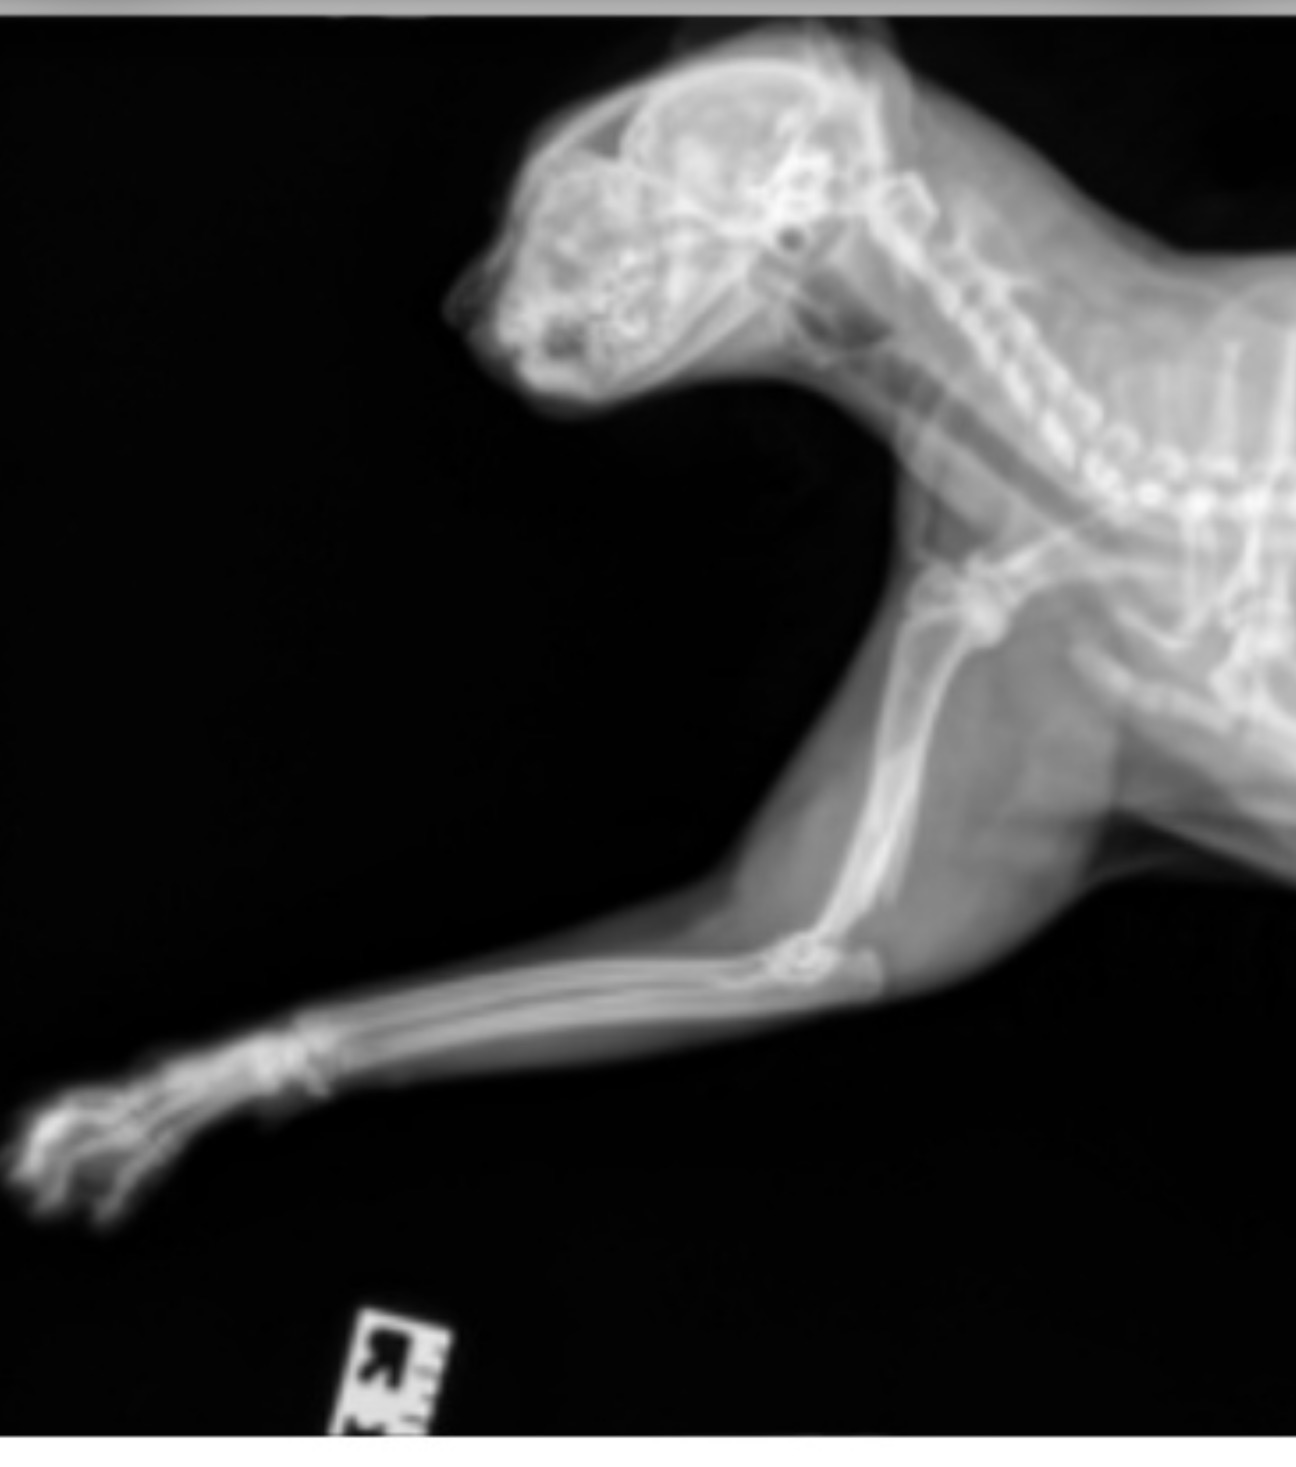

The X-rays show that Smokey Bear has suffered two significant breaks in his right forelimb:

• A closed complete displaced spiral fracture of the humeral diaphysis (the middle of the upper arm bone).

• A complete displaced fracture of the distal humerus (near the elbow joint).

Because the fractures are "displaced," the bones are no longer aligned. This means Smokey Bear requires having his front leg amputated which would increase his mobility and lessen the risk of him injuring himself .